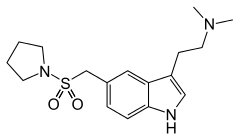

| Almotriptan | artificial | 5-(CH2SO2N(CH2)4) | CH3 | CH3 | N,N-dimethyl-2- [5-(pyrrolidin-1-ylsulfonylmethyl)- 1H-indol-3-yl]-ethanamine | 154323-57-6 |